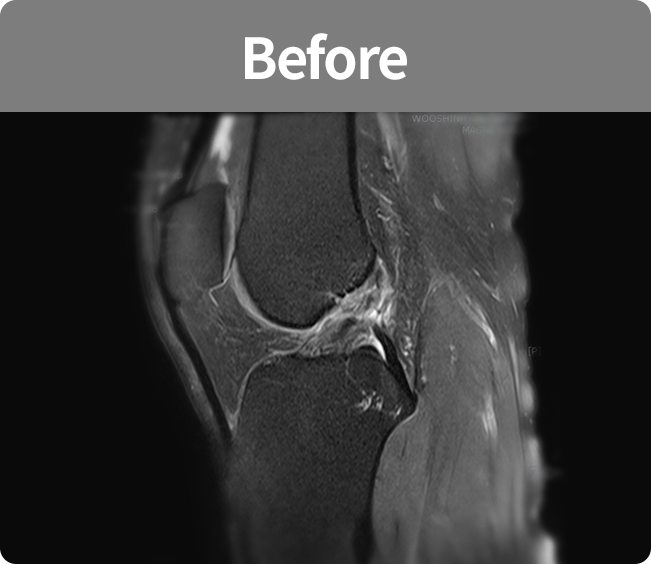

십자인대 재건술

무릎의 십자인대 손상에 자가 아킬레스건이나

동종(인공)인대를 사용하여 손상된 인대를

대체하게 하여 기능을 재건하는 수술법

(전방십자인대, 후방십자인대)

무릎의 십자인대 손상에 자가 아킬레스건이나 동종(인공)인대를 사용하여

손상된 인대를 대체하게 하여 기능을 재건하는 수술법(전방십자인대, 후방십자인대)